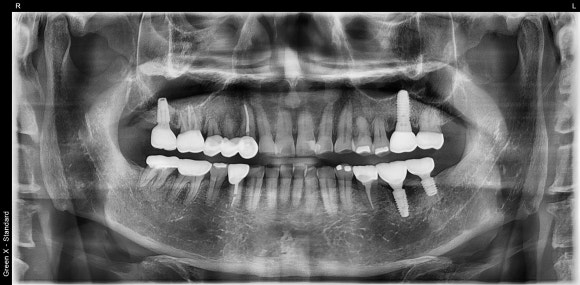

20250217

최종 파노라마 사진입니다.

- 워랜텍 임플란트를 사용했습니다. 출시 이후로 거의 변하지 않은 안정적인 디자인, 믿음직스러운 임상결과로 저는 워랜텍을 선호합니다.